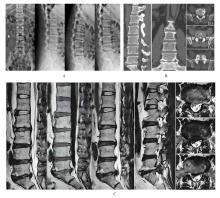

Jing ZENG,Yindong SONG,Zhiguo WANG,Aiju LOU,Dongdong WU,Bing XU,Jiayi LIU,Zili XIONG.

Comparison of clinical efficacy between unilateral biportal endoscopy and percutaneous endoscopic transforaminal discectomy in treatment of lumbar disc herniation

[J]. Journal of Jilin University(Medicine Edition), 2025, 51(5): 1349-1357.